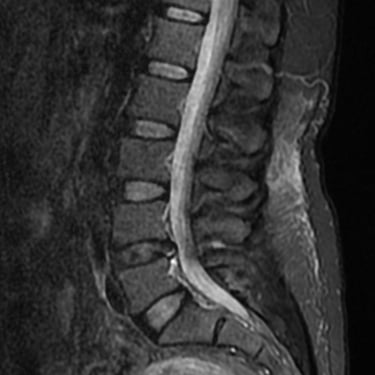

La hernia de disco lumbar se produce cuando el núcleo pulposo del disco intervertebral se desplaza y comprime las raíces nerviosas, generando dolor lumbar, ciática y debilidad en las piernas. El diagnóstico por resonancia magnética (RMN) es el método más preciso para identificar el nivel afectado y el grado de compresión nerviosa. Este estudio permite evaluar la morfología del disco, el canal vertebral y las estructuras adyacentes, orientando el tratamiento médico o quirúrgico. La detección temprana mediante RMN es fundamental para prevenir daño neurológico y planificar una intervención segura y efectiva en caso necesario.